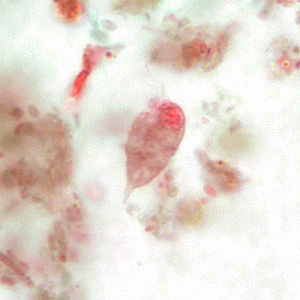

Chilomastix mesnili

pear shaped and posterior end tapers off to a point